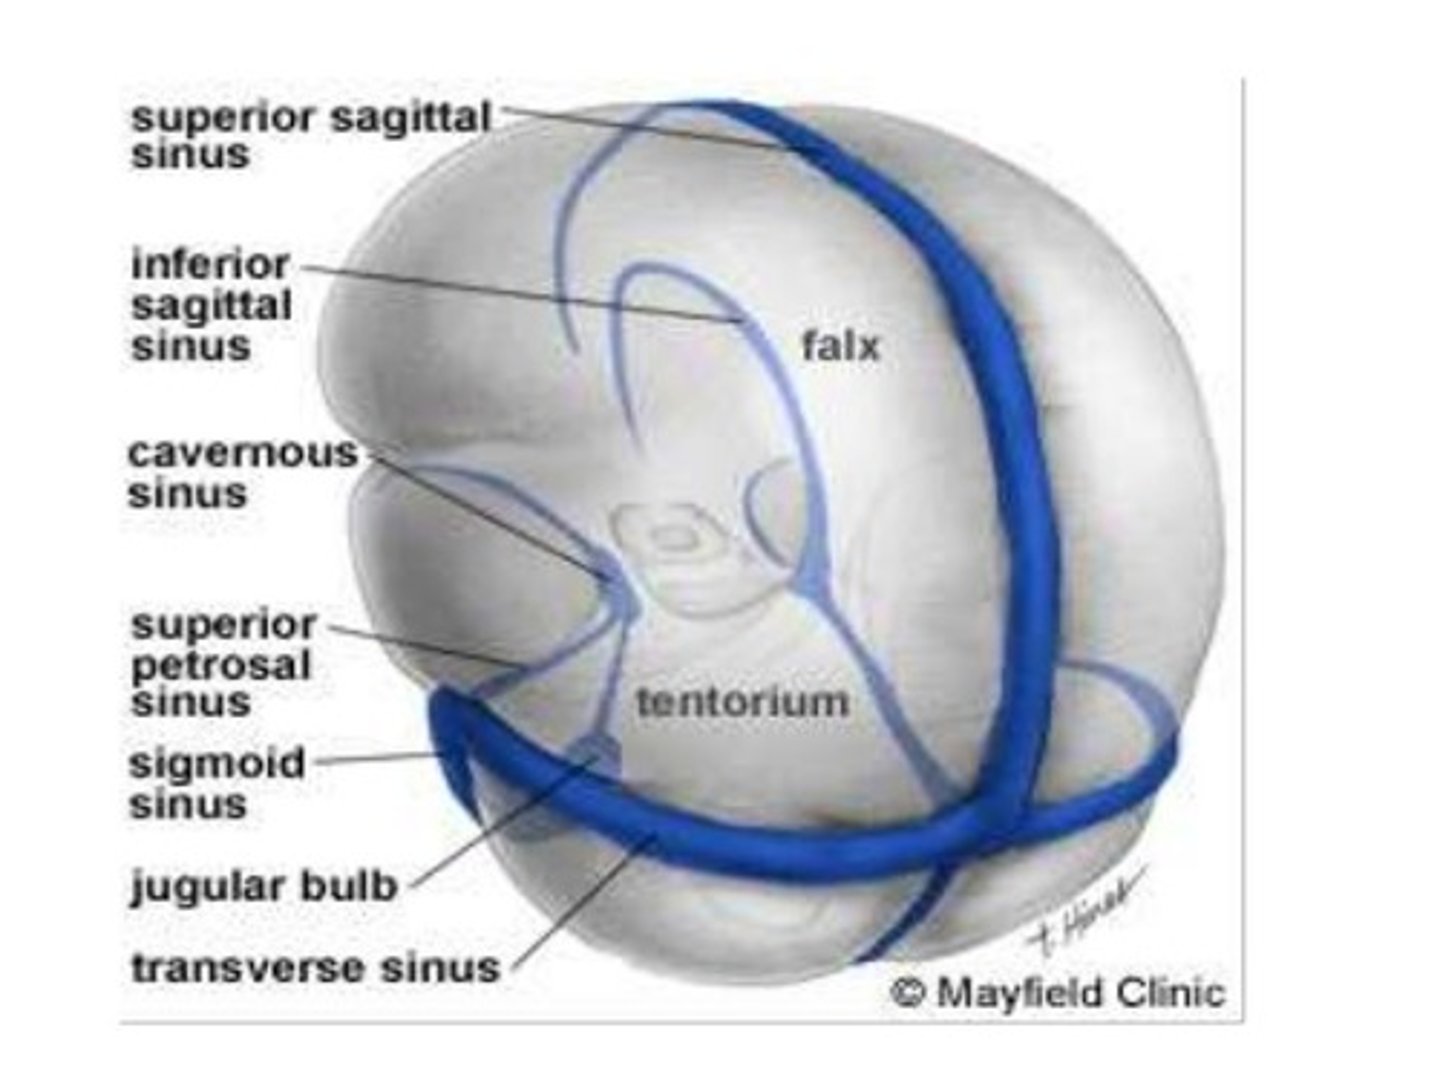

Dural sinuses

-Separates layers of cranial dura mater

-Collect blood circulating though brain

Cranial dura mater

-Outer periosteal

-Inner meningeal

-Folds inward to extend between parts of the brain

Cranial dura mater location

-Layers separated by dural sinuses

-Pressed closely against cranial bones